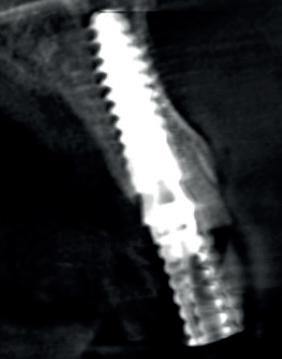

De implantaatplaatsing en de beslissende fout (afbeelding 1-13)

De extractie verliep voorspoedig, waarbij ik zoals al-

primaire stabiliteit van 60 Ncm.

11. Röntgenfoto ter controle van de plaatsing en de angulaire. Dit bone-level implantaat werd 4 mm onder de weke delen geplaatst.

tijd probeerde de buccale botlamel intact te houden. Dit is cruciaal voor latere botbehoud en implantaatplaatsing. Na curettage en spoelen van de alveole beoordeelde ik de situatie opnieuw: de botcondities leken gunstig voor een immediaat implantaat.

Hier begon echter de cruciale fout in mijn klinisch besluitvormingsproces. In mijn streven naar maximale primaire stabiliteit - wetende dat immediaat belasten enkel mogelijk is bij hoge stabiliteit -on-

derprepareerde ik de osteotomie. Dit betekende dat ik een iets te smal implantaatbed creëerde, in de hoop dat het implantaat stevig in het bot verankerd zou worden.

Op papier leek dit een logische stap: het MegaGen AnyRidge-implantaat dat ik koos, gaf me een stabiliteit van 60Ncm—een cijfer dat vertrouwen gaf in immediaat belasten. Maar in mijn enthousiasme had ik onvoldoende rekening gehouden met de biologische gevolgen van overmatige compressie.